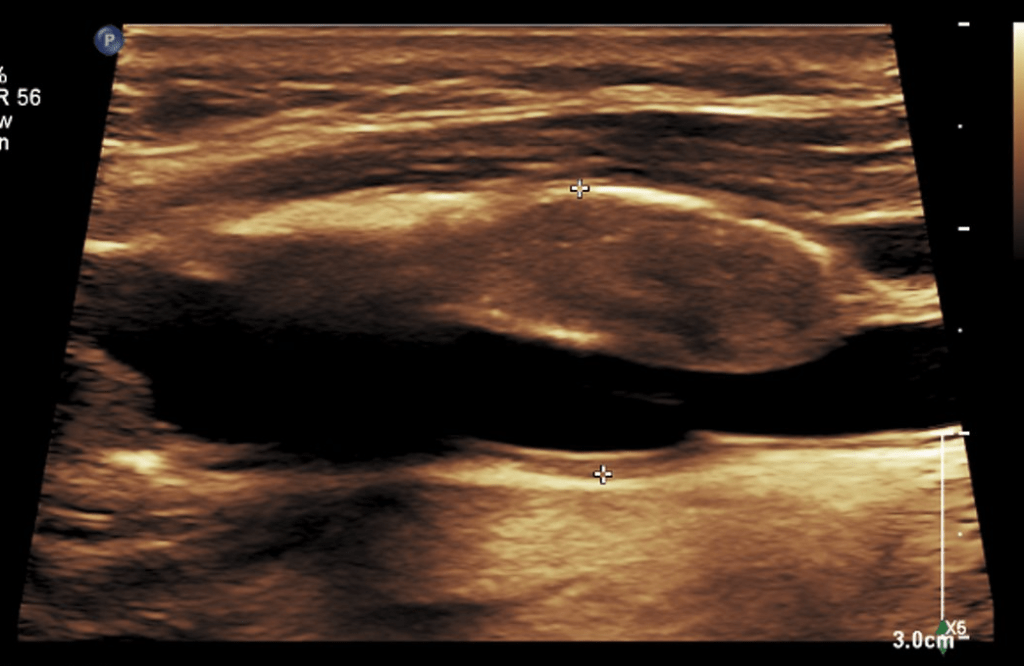

CTA tends to overread stenoses which was in the 60-79% range on duplex

The patient is a middle aged executive who complains of bouts of aphasia triggered by intense conversations and business meetings. It first occurred while driving to Dubai on a conference call. Since then, they occurred several times a week, typically triggered during meetings where he needs to think and speak. Casual conversation and cognition does not seem to trigger this. Workup revealed a heterogeneous plaque affecting the left ICA with velocities in the 60-79% range. CTA confirmed this plaque. MRI failed to show any stroke or other lesions. Neurology evaluation showed normal exam. The patient underwent endarterectomy, and had a normal recovery. In followup, he denied any further episodes of aphasia.